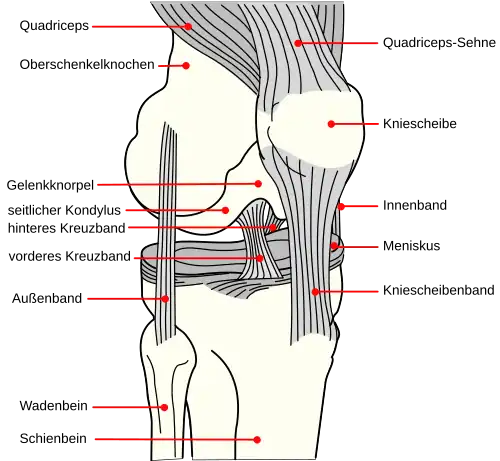

Das Kniegelenk (lateinisch Articulatio genus) ist das im Knie (lateinisch Genu, altgriechisch γόνυ gony) befindliche größte Gelenk der Säugetiere. Der Oberschenkelknochen (Femur), das Schienbein (Tibia) und die Kniescheibe (Patella) bilden dabei die knöchernen Gelenkkörper.

Das Kniegelenk ist ein zusammengesetztes Gelenk. Es besteht aus zwei Einzelgelenken, dem Kniescheibengelenk (Articulatio femoropatellaris), welches sich zwischen Oberschenkelknochen und Kniescheibe befindet, und dem Kniekehlgelenk (Articulatio femorotibialis), das zwischen Oberschenkelknochen und Schienbeinkopf (Caput tibiae) liegt. Anatomisch gesehen handelt es sich bei dem proximalen Gelenk zwischen Schienbein (Tibia) und Wadenbein (Fibula) (Articulatio tibiofibularis) zwar um ein eigenständiges Gelenk, das aber in der Regel über eine Ausbuchtung der Kniegelenkkapsel (Recessus subpopliteus) mit dem Kniegelenk verbunden ist.

Schienbein

Kniescheibe

Menisken

Man unterscheidet einen Innenmeniskus (Meniscus medialis), der C-förmig, größer und etwas unbeweglicher (da mit dem Innenband verwachsen) ist, und einen Außenmeniskus (Meniscus lateralis), der kreisförmig, kleiner und beweglicher ist (da er mit keinem Seitenband verwachsen ist). Die Menisken sind im Querschnitt keilförmig. Die hohe Kante liegt außen, die niedrige innen. Da die Oberschenkelknochen genau in der Mitte direkt auf dem Schienbeinplateau und peripher auf den Menisken aufliegen, tragen diese einen wesentlichen Teil der Last.

Bänder

Da das Knie durch seine knöcherne Konstruktion sehr instabil ist, wird es durch zahlreiche Bänder gesichert. Sie verstärken damit die Gelenkkapsel, in deren äußere Schicht sie in der Regel eingebaut sind. Die Bänder des Knies werden nach ihrer Lage in vordere (ventrale), seitliche (kollaterale), hintere (dorsale) und zentrale Bänder eingeteilt.

Seitliche Bandsicherung

Das Knie hat zwei Seitenbänder: ein inneres (Ligamentum collaterale tibiale) und ein äußeres (Ligamentum collaterale fibulare). In Streckstellung sind beide Seitenbänder (auch Kollateralbänder genannt) gespannt und verhindern somit die Drehbewegung, in Beugestellung verkleinert sich der Krümmungsradius, Ursprung und Ansatz nähern sich einander an und die Bänder sind infolgedessen entspannt. Beide Seitenbänder stabilisieren das Kniegelenk in seitlicher Richtung (Frontalebene), damit ein Wegknicken in eine O-Bein-Stellung (Genu varum) oder X-Bein-Stellung (Genu valgum) verhindert wird.

Das Innenband (Ligamentum collaterale tibiale bzw. mediale) ist ein dreieckiges, flaches Band, das breitflächig vom Aufsatz des inneren Oberschenkelknochens (Epicondylus medialis femoris) zur Innenseite des Schienbeines (Facies medialis tibiae) verläuft. Es ist in die äußere Schicht der Gelenkkapsel eingebaut und mit dem Innenmeniskus verwachsen.

Das Außenband (Ligamentum collaterale fibulare bzw. laterale) ist ein kräftiges Band, das in seinem dorsalen Abschnitt zylinderförmig vom Aufsatz des seitlichen Oberschenkelknochens (Epicondylus lateralis femoris) zum Wadenbeinkopf (Caput fibulae) zieht. Es hat keine feste Verbindung zur Gelenkkapsel und den Menisken.

Zentrale Bandsicherung

Die Kreuzbänder (Ligamenta cruciata) ziehen von der Grube zwischen den Oberschenkelknorren zum Schienbein. Von der Seite und von vorn betrachtet überkreuzen sie sich dabei in ihrem Verlauf.

Vorderes Kreuzband

Hinteres Kreuzband

Strecker

Beuger